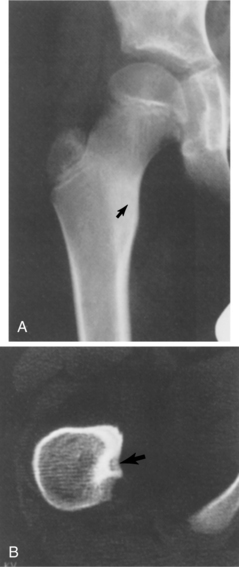

Osteoid osteoma is a rare benign vascular osteoblastic lesion. It is often found in the cortex of long bones such as the femur and tibia but may occur in almost any bone except the skull. The tumors occur near the end of the diaphysis (Fig. 26-4). Osteoid osteoma accounts for about 10% to 12% of benign bone tumors. Most of these lesions are found in men under the age of 25. The cause of osteoid osteoma remains unknown.

Figure 26-4 Osteoid osteoma. A, Bony sclerosis with cortical thickening is seen in this person with pain in the proximal femur. A faint lucency (arrow) can be seen in the area of sclerosis, which is the nidus of an osteoid osteoma. B, A computed tomographic (CT) scan through the nidus shows it to lie just dorsal to the lesser trochanter (arrow). This is a characteristic appearance of an osteoid osteoma with CT. (From Helms C: Fundamentals of skeletal radiology: benign cystic lesions, Philadelphia, 1989, WB Saunders.)